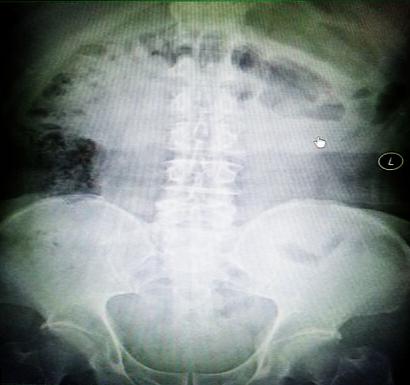

受試患者在結(jié)腸端端吻合術(shù)中,使用我司新研制產(chǎn)品達(dá)到了理想的預(yù)期效果。患者術(shù)后7天、14天X光片顯影,可降解腸道支架均能按研制設(shè)計(jì)的預(yù)期時(shí)間節(jié)點(diǎn)保持應(yīng)有強(qiáng)度,術(shù)后21天X光片顯示可降解腸道支架已完全破碎,并排出體外。在整個(gè)試驗(yàn)過程中,病患無任何不良反映,耐受良好。